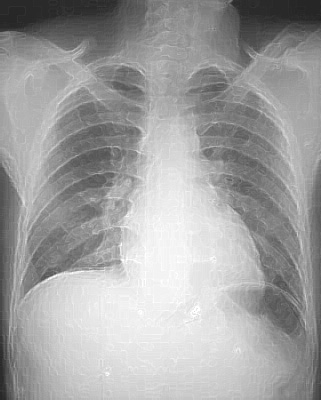

Image analoque d'une cliche pulmonaire de face :